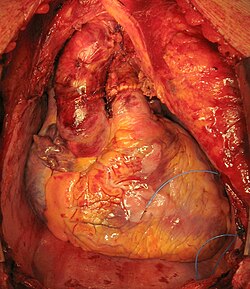

Donor ürəyinin xəstənin döş qəfəsində yerləşdirilməsi (biatrial texnika)

Xəstənin döş qəfəsində bikaval metodu ilə köçürülmüş ürək

Hal-hazırda ürək transplantasiyası üçün bir çox variantlar hazırlanmışdır, lakin onlardan yalnız ikisi geniş istifadə olunur: biatrial (iki atrial) və daha müasir bikaval texnikaları.

Güman edilir ki, bikaval texnikasından istifadə ürək transplantasiyasından sonra xəstədə ritm və keçiricilik pozutuları riskini azalda bilər.